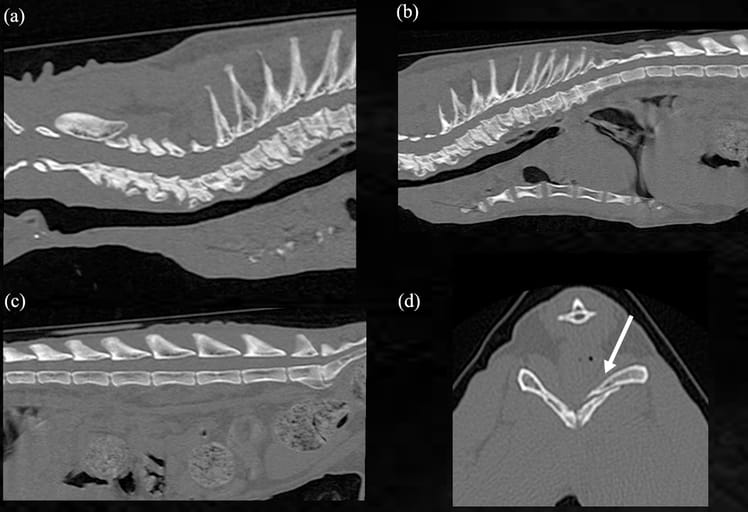

Figure 2 CT imaging of the cat. Sagittal plane of CT of the (a) cervical, (b) thoracic and (c) lumbar spine. Vertebral exostoses

and extensive osteophytes were seen in the cervical and thoracic spine. Spondylosis was also seen at the lumbosacral

junction. (d) Transverse CT image of the pelvis. A bone fracture was seen (indicated by the arrow)